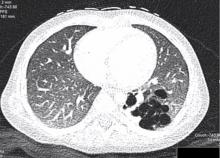

A 14-month-old female patient (full term, normal vaginal delivery) was diagnosed antenatally with left side congenital pulmonary airway malformation. The postnatal workup, including chest CTA, showed left lower lobe (LLL) congenital pulmonary airway malformation and arterial supply of the LLL from a large artery arising directly from the descending aorta. A uniportal thoracoscopic lobectomy of the left lower lobe was performed, with lung isolation achieved using single lumen endotracheal intubation of the right main bronchus.